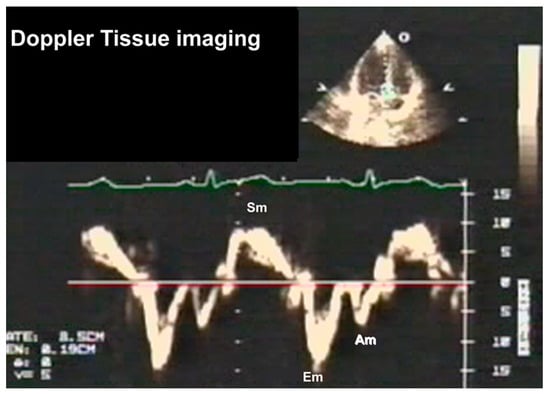

3.2.3. Doppler Tissue Imaging (DTI)

- Gorcsan, J., 3rd. Tissue Doppler echocardiography. Curr. Opin. Cardiol. 2000, 15, 323–329. [Google Scholar] [CrossRef] [PubMed]